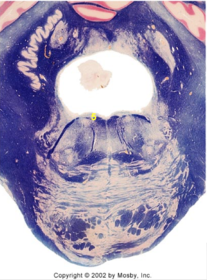

| Longitudinal pontine fibers (corticospinal tract) | |

| Transverse pontine fibers (dark fibers) | |

| Pontine nuclei (pale) | |

| Medial lemniscus | |

| ALS | |

| Trapezoid body | |

| Ventral trigeminothalamic tract | |

| Superior olive | |

| Central tegmental tract | |

| Facial nerve root fibers - descending | |

| Facial motor nucleus | |

| Interposed nuclei | |

| Medial longitudinal fasciculus | |

| Facial nerve root - internal genu | |

| Abducens nucleus | |

| Lateral vestibular nucleus | |

| Superior vestibular nucleus | |

| Inferior cerebellar peduncle | |